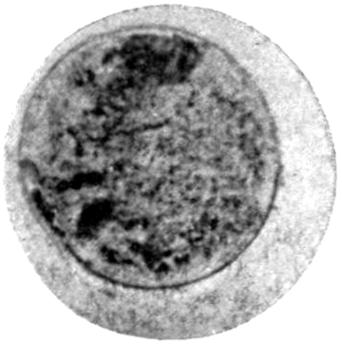

The Mechanism of Lead Absorption.

—The final method of absorption of lead particles or lead solution into the animal body remains to be considered. Experimental phagocytosis of lead particles—as, indeed, of any minute particles of substance—suspended in an isotonic solution, may be observed directly under the microscope. Lead particles show no exception to the rule, and white blood-corpuscles in a hanging-drop preparation, made by suspending them in an isotonic salt solution and serum, may be watched englobing particles of lead, and by appropriate means the ingested lead may be afterwards demonstrated. In such an experiment, much of the lead absorbed by the individual corpuscles rapidly loses its property of giving a black precipitate with sulphuretted hydrogen, and has apparently become converted into an organic compound, peptonate or albuminate.

In the section devoted to the Chemistry of Lead, it has been[21] noted that the colloidal solutions of lead are not precipitated by sulphuretted hydrogen, and that albuminates and peptonates of lead are presumably of colloidal form. There seems evidence, therefore, that the direct absorption of lead takes place by means of the phagocytes of the body, and that in them it becomes converted into a colloidal form, in which it is probably eliminated through the kidney and intestine, mainly the latter.

Further evidence of the englobement of lead particles by amœbic cells may be gained if sections of the intestines of experimental animals are examined; in the lymphoid glands particles of lead may be seen situated in the interior of the walls, and even in the cells. It does not by any means follow that these particles of lead sulphide present in the cells have been formed in situ; more probably the lead has been converted into a sulphide in the intestinal lumen itself, and subsequently taken up by the amœbic cells situated in its periphery.